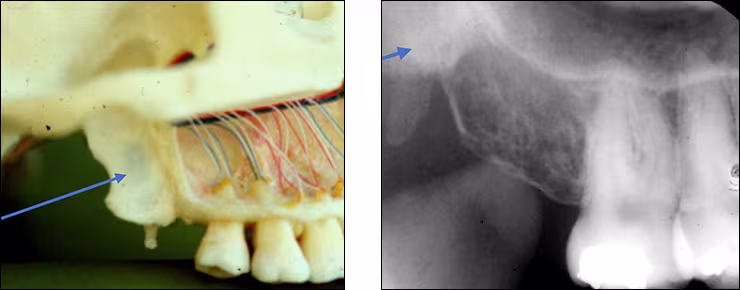

Maxillary sinus – The maxillary sinus is one of the paired paranasal sinuses. This prominent radiolucent air-filled cavity is located above the posterior teeth on the right and left sides of the maxilla. The sinus cavities are horizontally oblong bilateral structures with fine radiopaque borders. The maxillary sinus may contain septa which appear as radiopaque lines within the body of the sinus cavity. The size of the maxillary sinus can be quite variable and sometimes encroaches into the alveolar process, especially when posterior teeth are missing. Typically, the sinus appears uniform right to left. The maxillary sinus is sometimes referred to as the maxillary antrum and can be observed on both maxillary premolar and molar periapical images and partially on lateral-canine periapical images.

Zygomatic bone – The zygomatic bone or cheek bone attaches to the right and left sides of the posterior maxilla. The zygomatic bone, quadrangular in shape, broadens as it extends posteriorly. This bilateral radiopaque structure is also known as the malar bone. The zygomatic bone can be seen on maxillary premolar and molar periapical images.

Zygomatic process - The zygomatic process is the radiopaque U-shaped structure representing where the zygomatic bone attaches to the maxilla. The zygomatic process of the maxilla is the most anterior aspect of the zygomatic bone. The process is positioned toward the midline while the bone extends posteriorly away from the midline. This structure is sometimes referred to as the malar process and can be seen on maxillary premolar and molar periapical images.